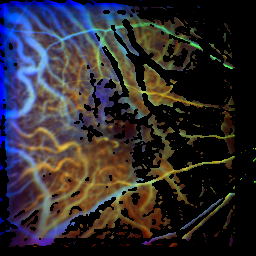

Responder

| before the first rheopheresis |

| time of the maximum: 55.4 f ± 10.1%visual acuity: 0.50

time of the maximum: 53.3 f ± 14.5%visual acuity: 0.63

time of the maximum: 34.7 f ± 13.8%visual acuity: 0.80